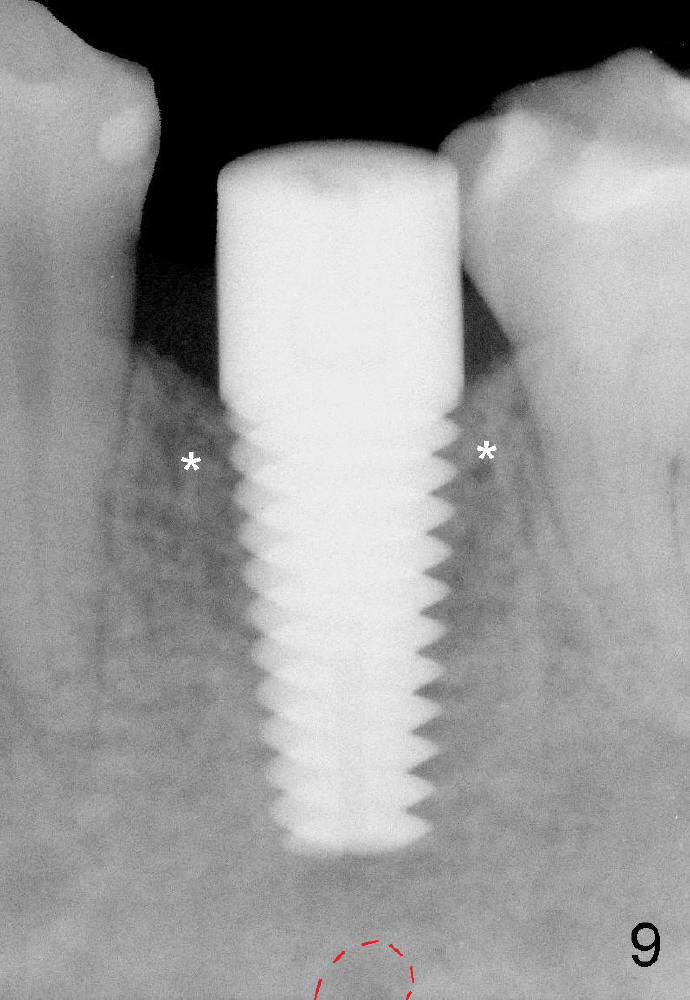

Fig.9 (6 months postop): Bone density around the coronal aspect of the implant increases (*). Apical resorption occurs.